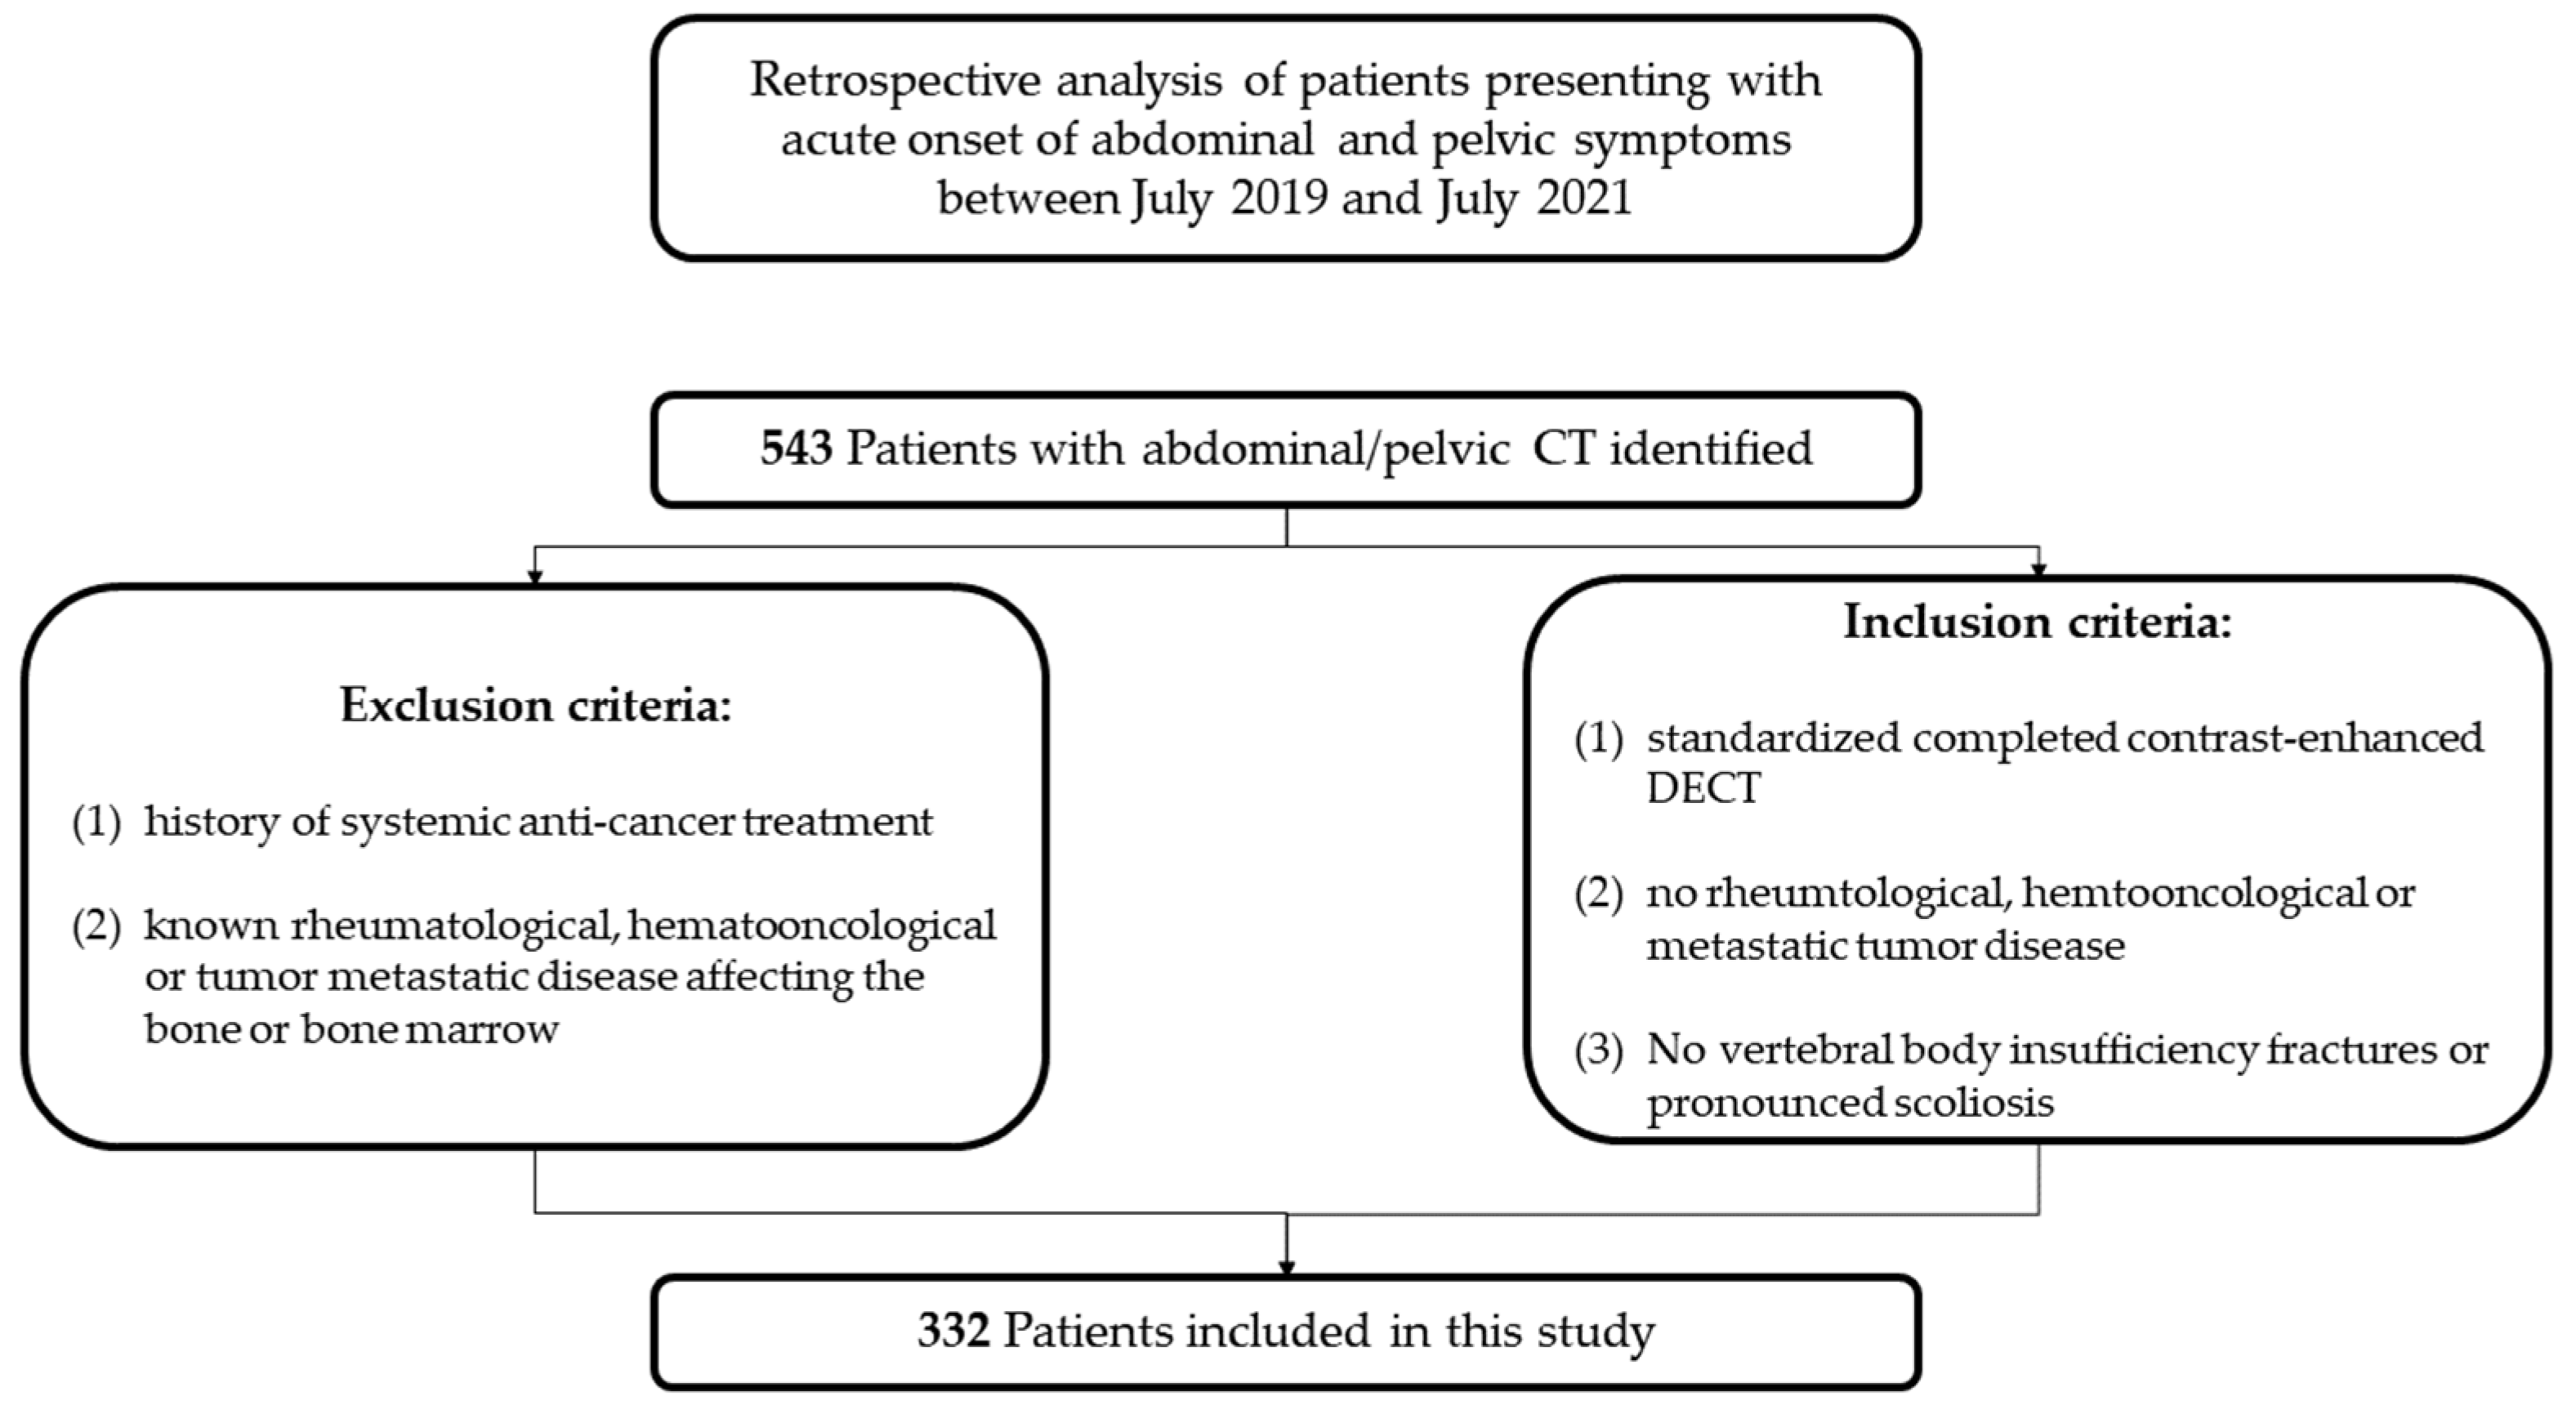

2. Materials and Methods

2.1. Patients